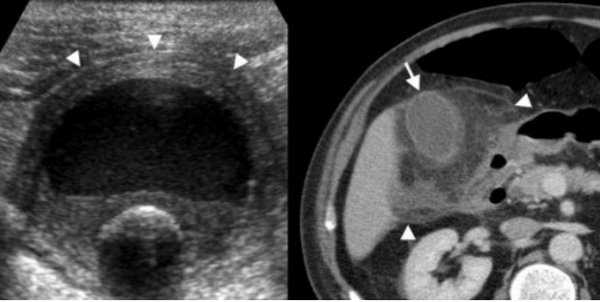

Слева — УЗИ — желчного пузыря у 59 летней женщины с острым холециститом. Субсерозный отек так, как гипоэхогенное утолщение между гиперэхогенными слоями (мышечным и слизистым). Справа — КТ брюшной полости с контрастным усилением. Также визуализируется субсерозный отек так, как наружный слой гиподенсный.

Острый холецистит стоит на четвертом месте среди заболеваний брюшной полости, требующих немедленной госпитализации. Если на УЗИ у пациентов, поступивших с острым животом, визуализируется утолщение стенки желчного пузыря, то первое о чем думают радиологи — это острый холецистит. Для постановки диагноза холецистита должны присутствовать также следующие признаки, как на УЗИ, так и на КТ:

Острый калькулезный холецистит. После контрастного усиления визуализируется растянутый желчный пузырь (белые наконечники) со слегка утолщенной стенкой. Визуализируется камень в шейки желчного пузыря (белая стрелка).